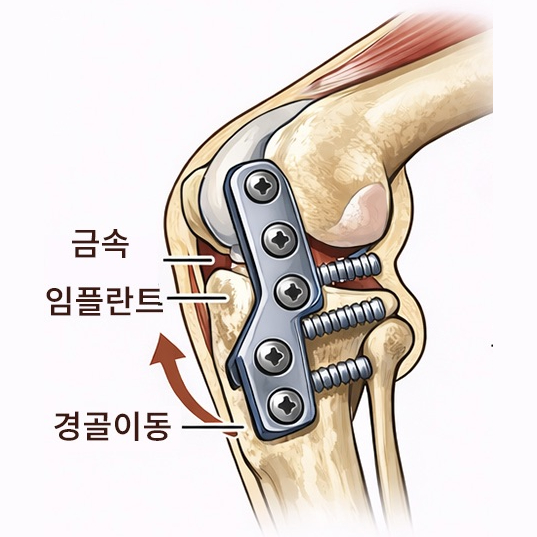

슬개골 탈구 수술은 단순히 빠진 뼈를 제자리로 돌려놓는 수술이 아닙니다.

무릎 관절의 정렬, 뼈의 구조, 연부조직 상태를 종합적으로 판단해 아이에게 맞는 수술 계획이 필요합니다.

슬개골 탈구 수술은 정확한 진단과 수술 환경이 결과를 좌우합니다.

본원은 정형외과 수술을 고려한 장비와 시스템을 갖추고 있으며,

수술 전·후 방사선 검사를 통해 관절 정렬과 수술 결과를 객관적으로 평가합니다.